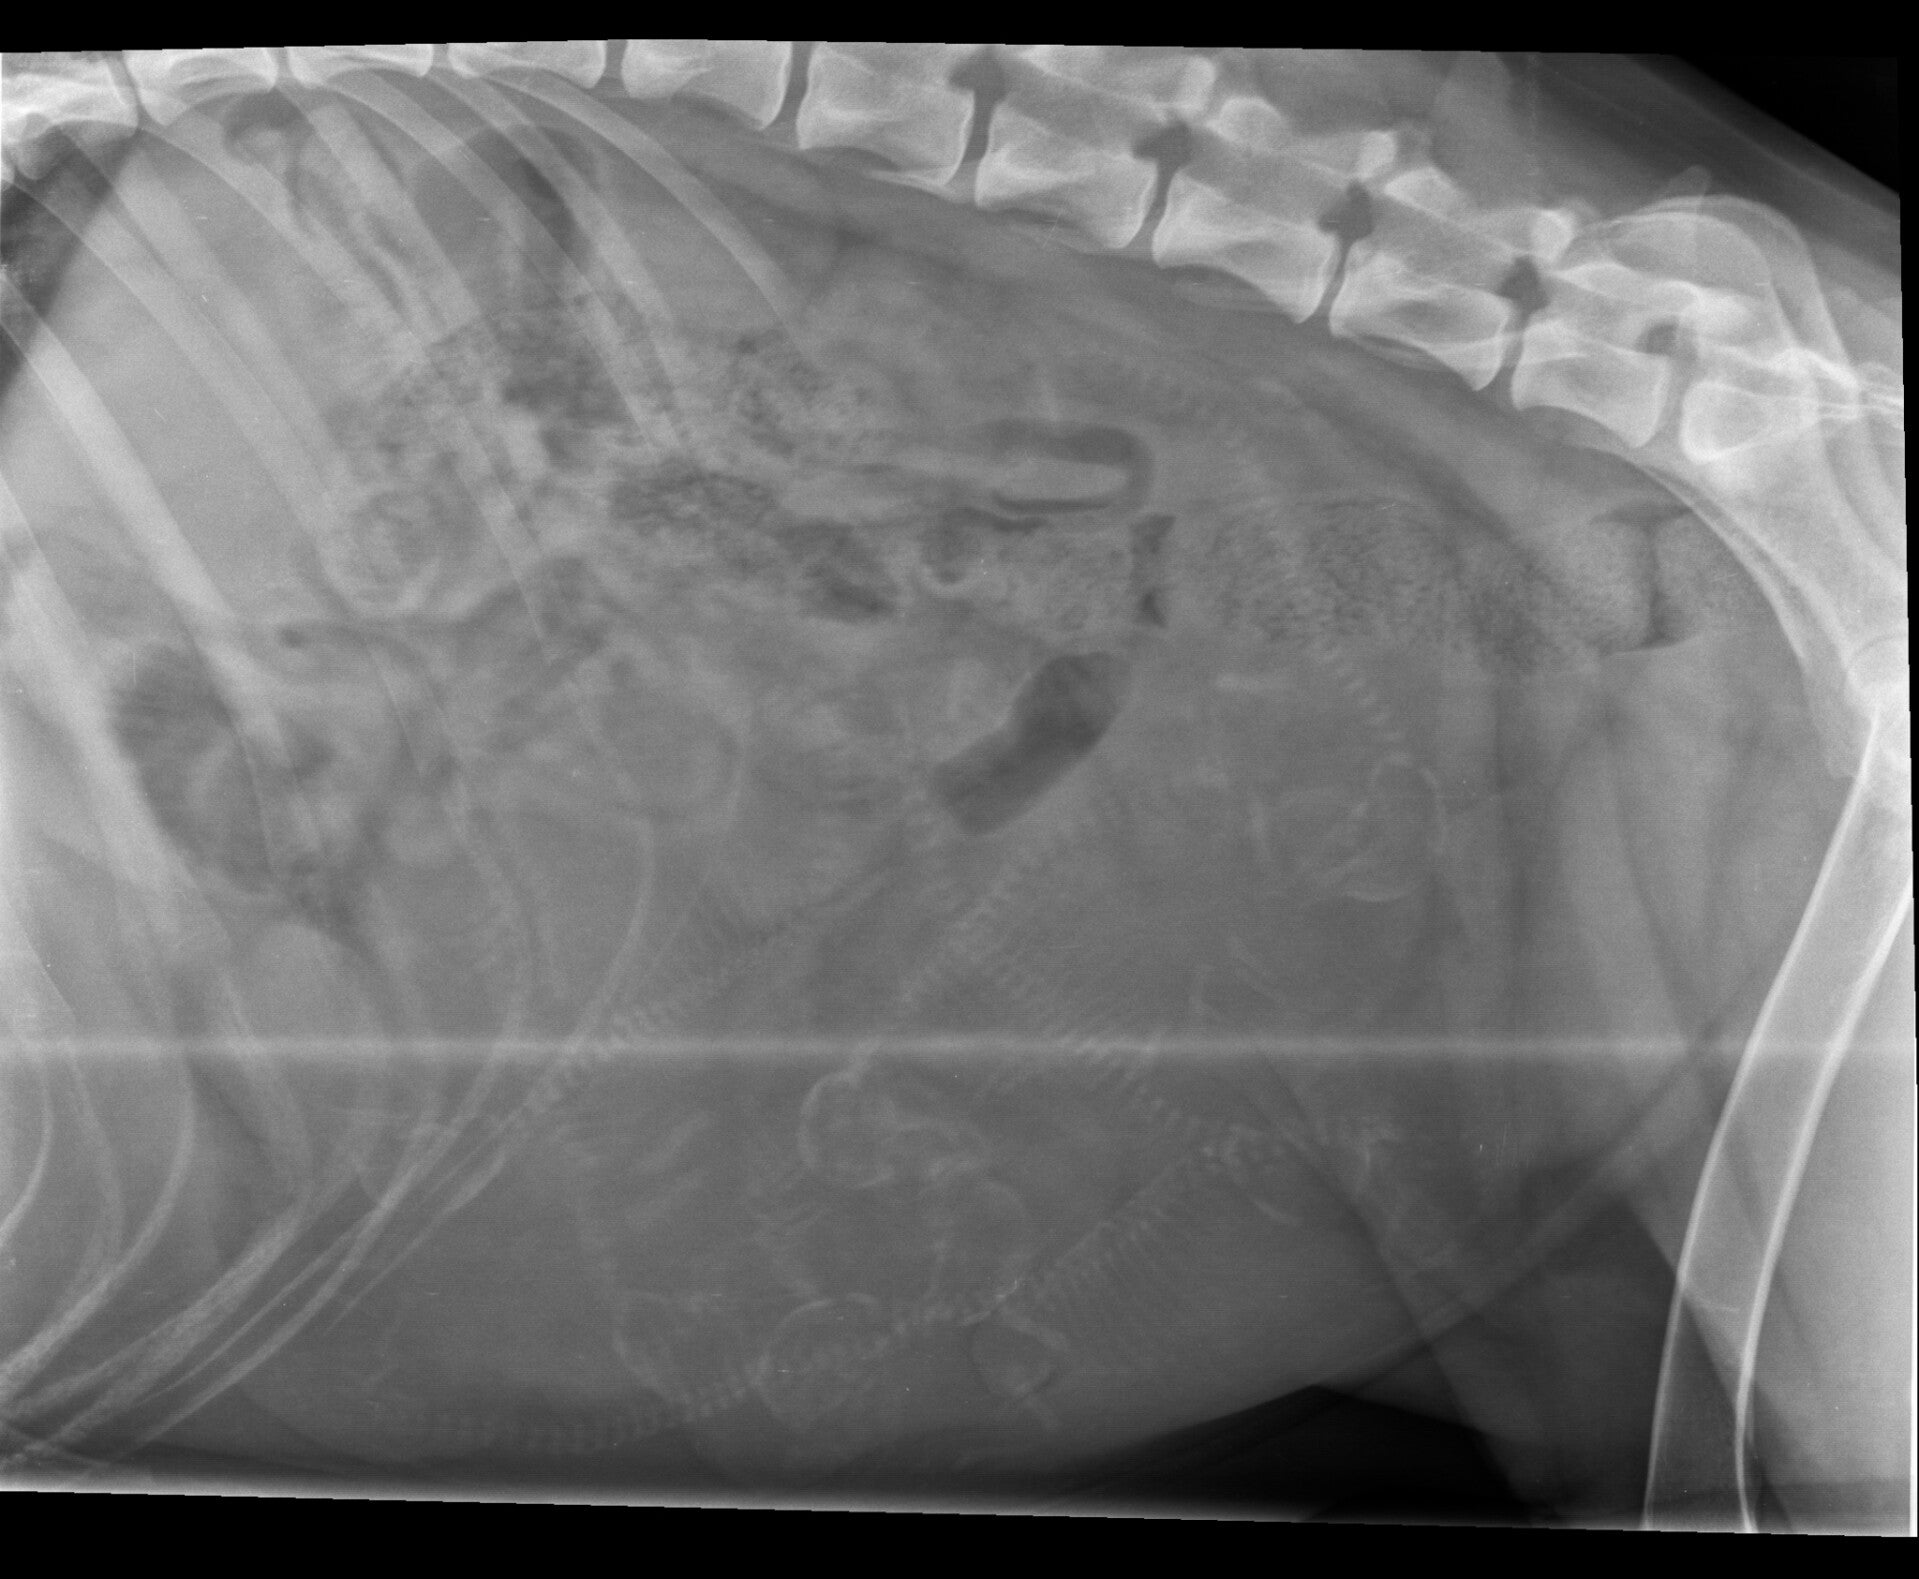

Röntgenfoto

Vandaag (25 januari) gingen we met Norah nog een keer naar de dierenarts, dit keer voor de röntgenfoto. Op de röntgenfoto kunnen we zien hoeveel pups Norah ongeveer krijgt. Hoeveel pups telt u? ;)